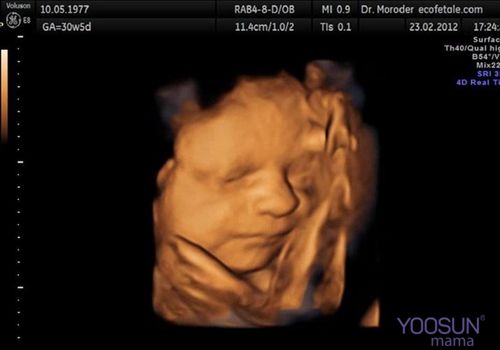

Siêu âm 3D là kỹ thuật siêu âm cho thấy các hình ảnh 3 chiều về những chuyển động đang xảy ra bên trong cơ thể mẹ và bé. Nếu như siêu âm 2D chỉ cho ra 2 hình ảnh đen trắng thì siêu âm thai 3D có thêm hình màu rõ ràng và sắc nét.

Về cơ bản, siêu âm 3D sử dụng sóng âm phát ra từ máy siêu âm 3D cho phép chụp những hình ảnh ở nhiều góc độ khác nhau. Thông qua việc siêu âm, bạn có thể quan sát tương đối rõ hình hài thai nhi từ những đường nét trên gương mặt, chân, tay, mũi.

Hình ảnh siêu âm 3D

Ngoài ra, với kỹ thuật siêu âm này còn cho phép bác sĩ chẩn đoán được chiều dài, rộng và chiều sâu, chi tiết hình thái thai nhi bên trong bụng mẹ.